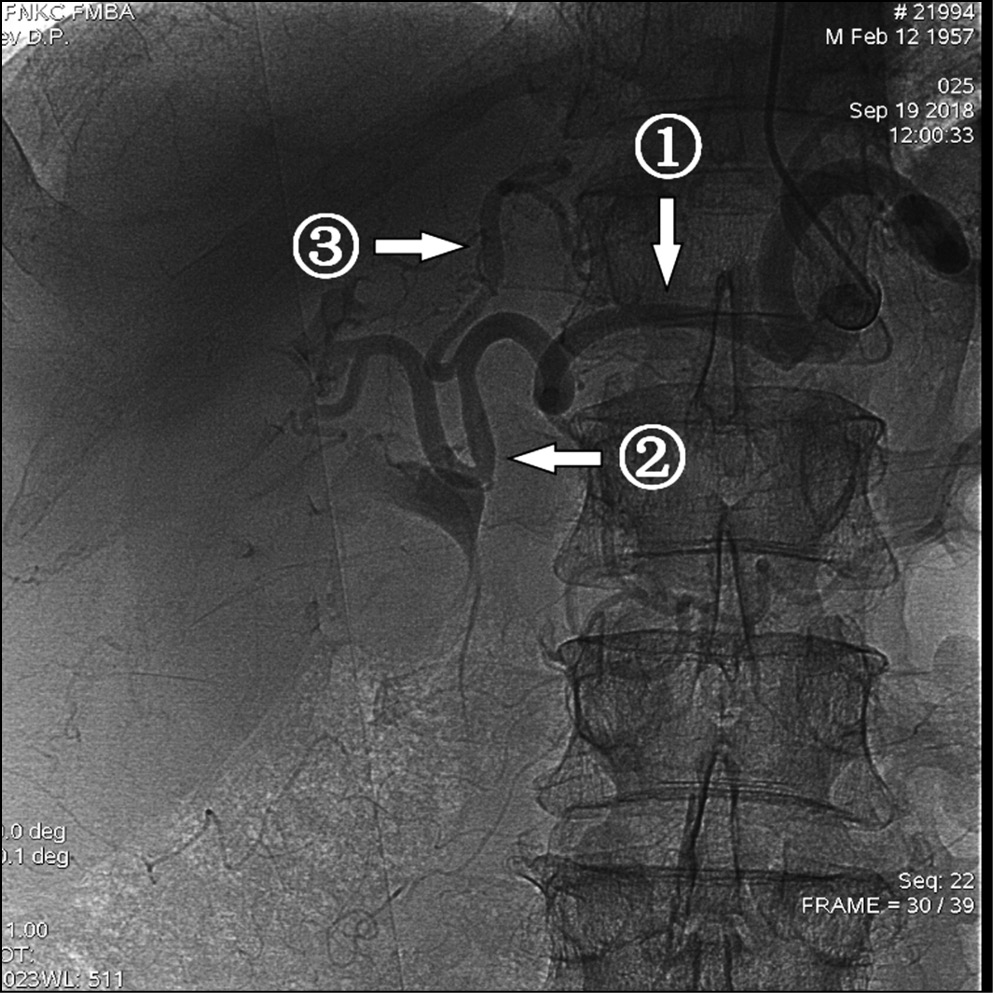

Однако при планировании химиоэмболизации артерий печени необходимо учитывать не только различные варианты кровоснабжения печени, но и особенности пробега висцеральных артерий. Так, у одного пациента была обнаружена повышенная извитость печеночных артерий, что исключало бы проведение ХЭПА в монолобарном варианте (рис. 3).

Рис. 3. Вариант кровоснабжения печени, выраженная извитость печеночных артерий

Примечание. 1 — общая печеночная артерия, 2 — правая печеночная артерия, 3 — левая печеночная артерия.

Микрокатетерная техника катетеризации позволила выполнить первоначальный план доступа в дистальное сосудистое русло (рис. 4).

Рис. 4. Селективная катетеризация сегментарных ветвей левой печеночной артерии при выраженной извитости печеночных артерий

Примечание. 1 — ангиографический катетер 5F в устье чревного ствола, 2 — микрокатетер, проходящий из чревного ствола в левую печеночную артерию, 3 — сегментарные ветви левой печеночной артерии.